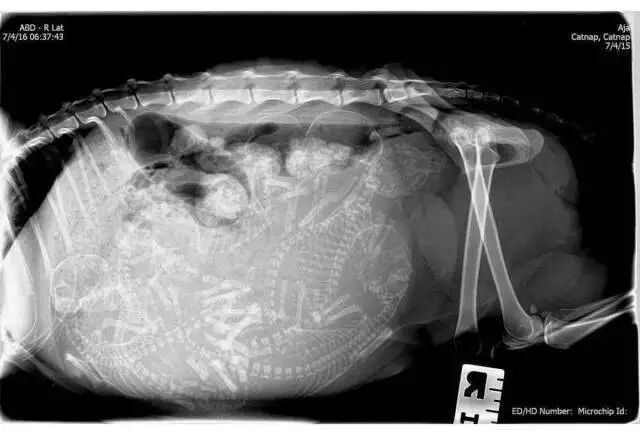

怀孕的猫

还是猫